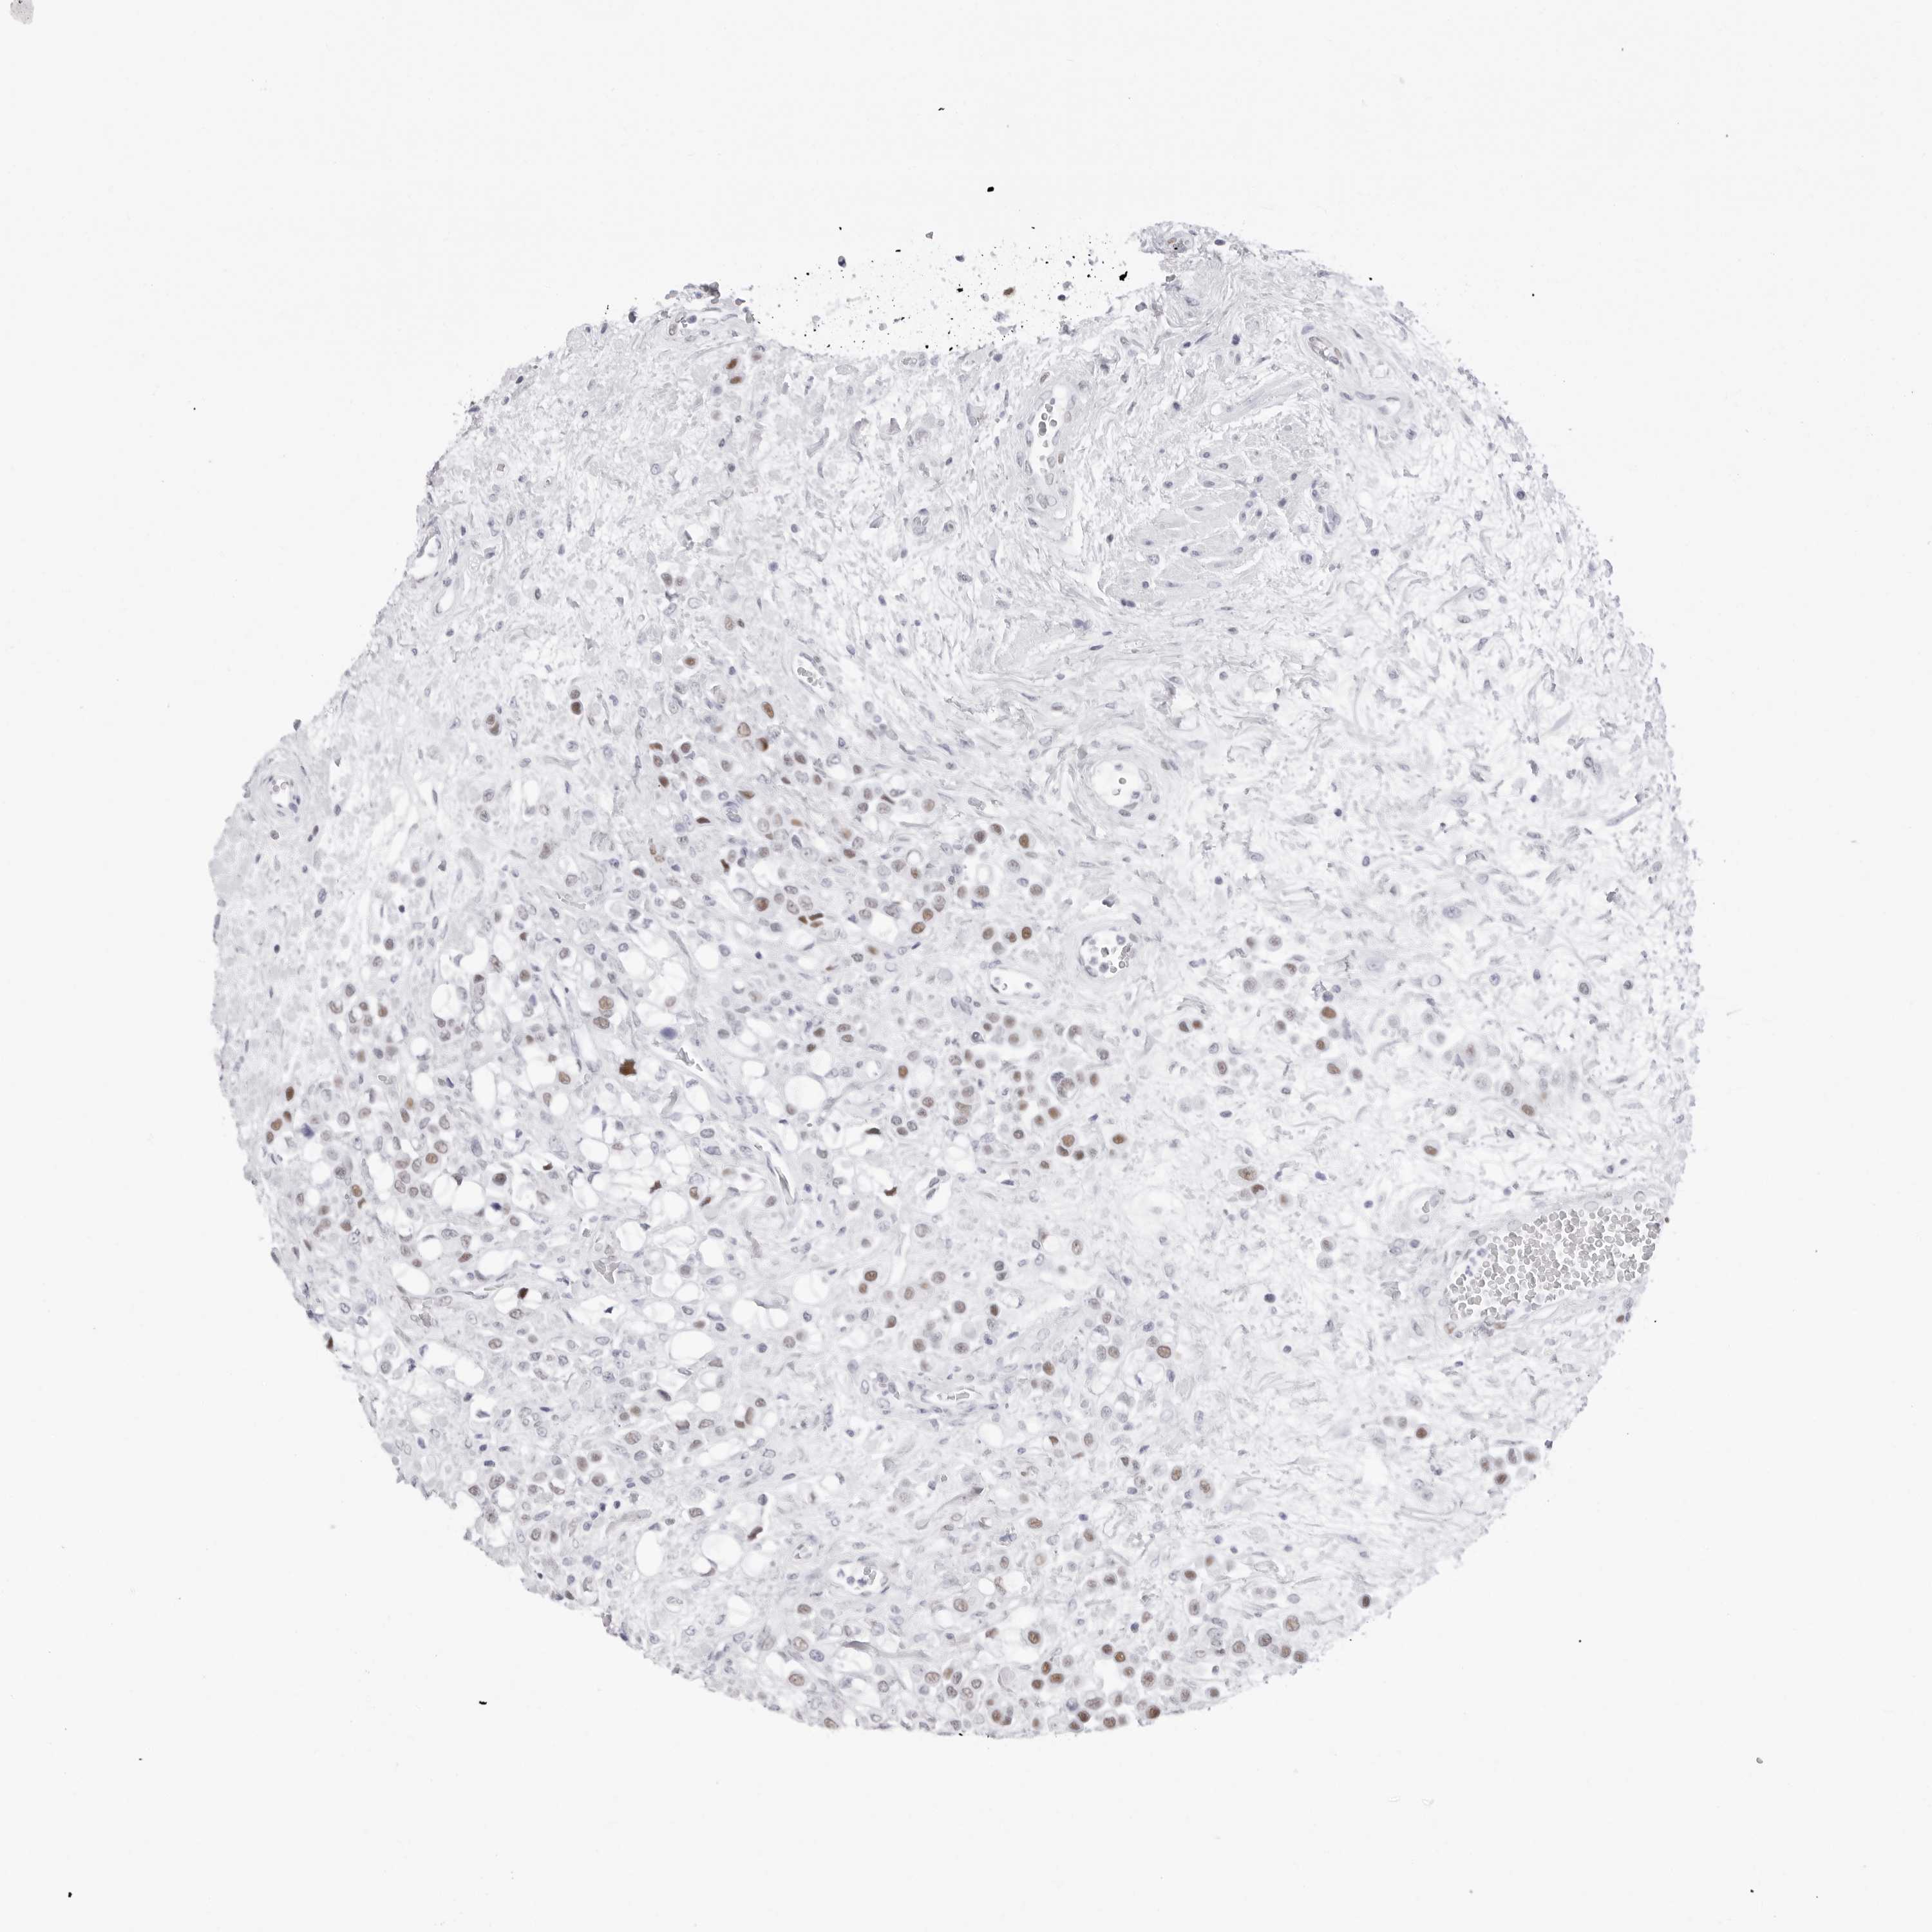

UROTHELIAL CANCER - Protein expressioni

A mouse-over function shows sample information and annotation data. Click on an image to view it in a full screen mode. Samples can be filtered based on level of antibody staining by selecting one or several of the following categories: high, medium, low and not detected. The assay and annotation is described here.

Note that samples used for immunohistochemistry by the Human Protein Atlas do not correspond to samples in the TCGA dataset.

Antibody stainingi

Antibody staining in the annotated cell types in the current human tissue is reported as not detected, low, medium, or high, based on conventional immunohistochemistry profiling in selected tissues. This score is based on the combination of the staining intensity and fraction of stained cells.

Each image is clickable and will lead to virtual microscopy that enables deeper exploration of all samples and also displays staining intensity scores, fraction scores and subcellular localization as well as patient and tissue information for each sample.

Antibody HPA028136

Antibody HPA030518

Antibody HPA030520

Staining

High

Medium

Low

Not detected

Intensity

Strong

Moderate

Weak

Negative

Quantity

>75%

75%-25%

<25%

None

Location

Nuclear

Cytoplasmic/membranous

Cytoplasmic/membranous,nuclear

Urothelial carcinoma, Low grade

Urothelial carcinoma, High grade